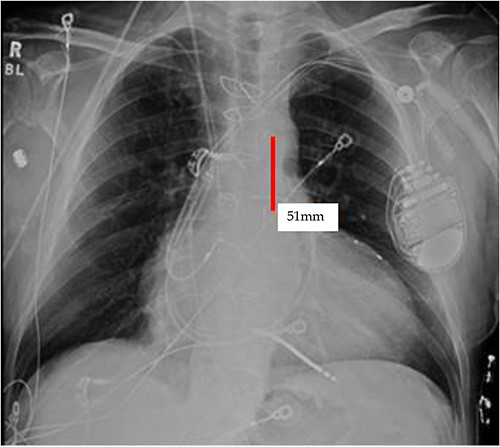

TEE guidance and fluoroscopy were used during the insertion of this patient’s left axillary IABP. The TEE note post-IABP insertion states that ‘the balloon is seen from the distal end of the aortic arch extending into the descending aorta.’ A same-day post-insertion CXR in the ICU showed a shortened IABP at about 5.1 cm long, indicating that the balloon must have been folded over itself to allow both markers to be so close to each other (Fig. 4).

Initial CXR: note the proximal and distal radiopaque markers of the IABP are visualized a few centimeters (5.1 cm) from each other; the proximity of the two markers indicates that along the path of the IABP, it has folded over itself causing the two markers to be abnormally close, as the 8Fr. balloon is 258 mm long, thus the markers should be separated by that much.